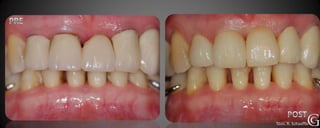

Prótesis Fija Convencional

Restauraciones periféricas totales “coronas”

Las coronas son restauraciones que involucran la totalidad del

diente, confeccionadas fuera de la boca (indirectas totales) que

luego son adheridas al diente en tratamiento. Pueden ser de

diversos materiales, cerámicas, composite y/o metálicas.

Prótesis Fija Convencional Restauracionesperiféricas totales “coronas” Las coronas son restauraciones que involucran la totalidad del diente, confeccionadas fuera de la boca (indirectas totales) que luego son adheridas al diente en tratamiento. Pueden ser de diversos materiales, cerámicas, composite y/o metálicas.